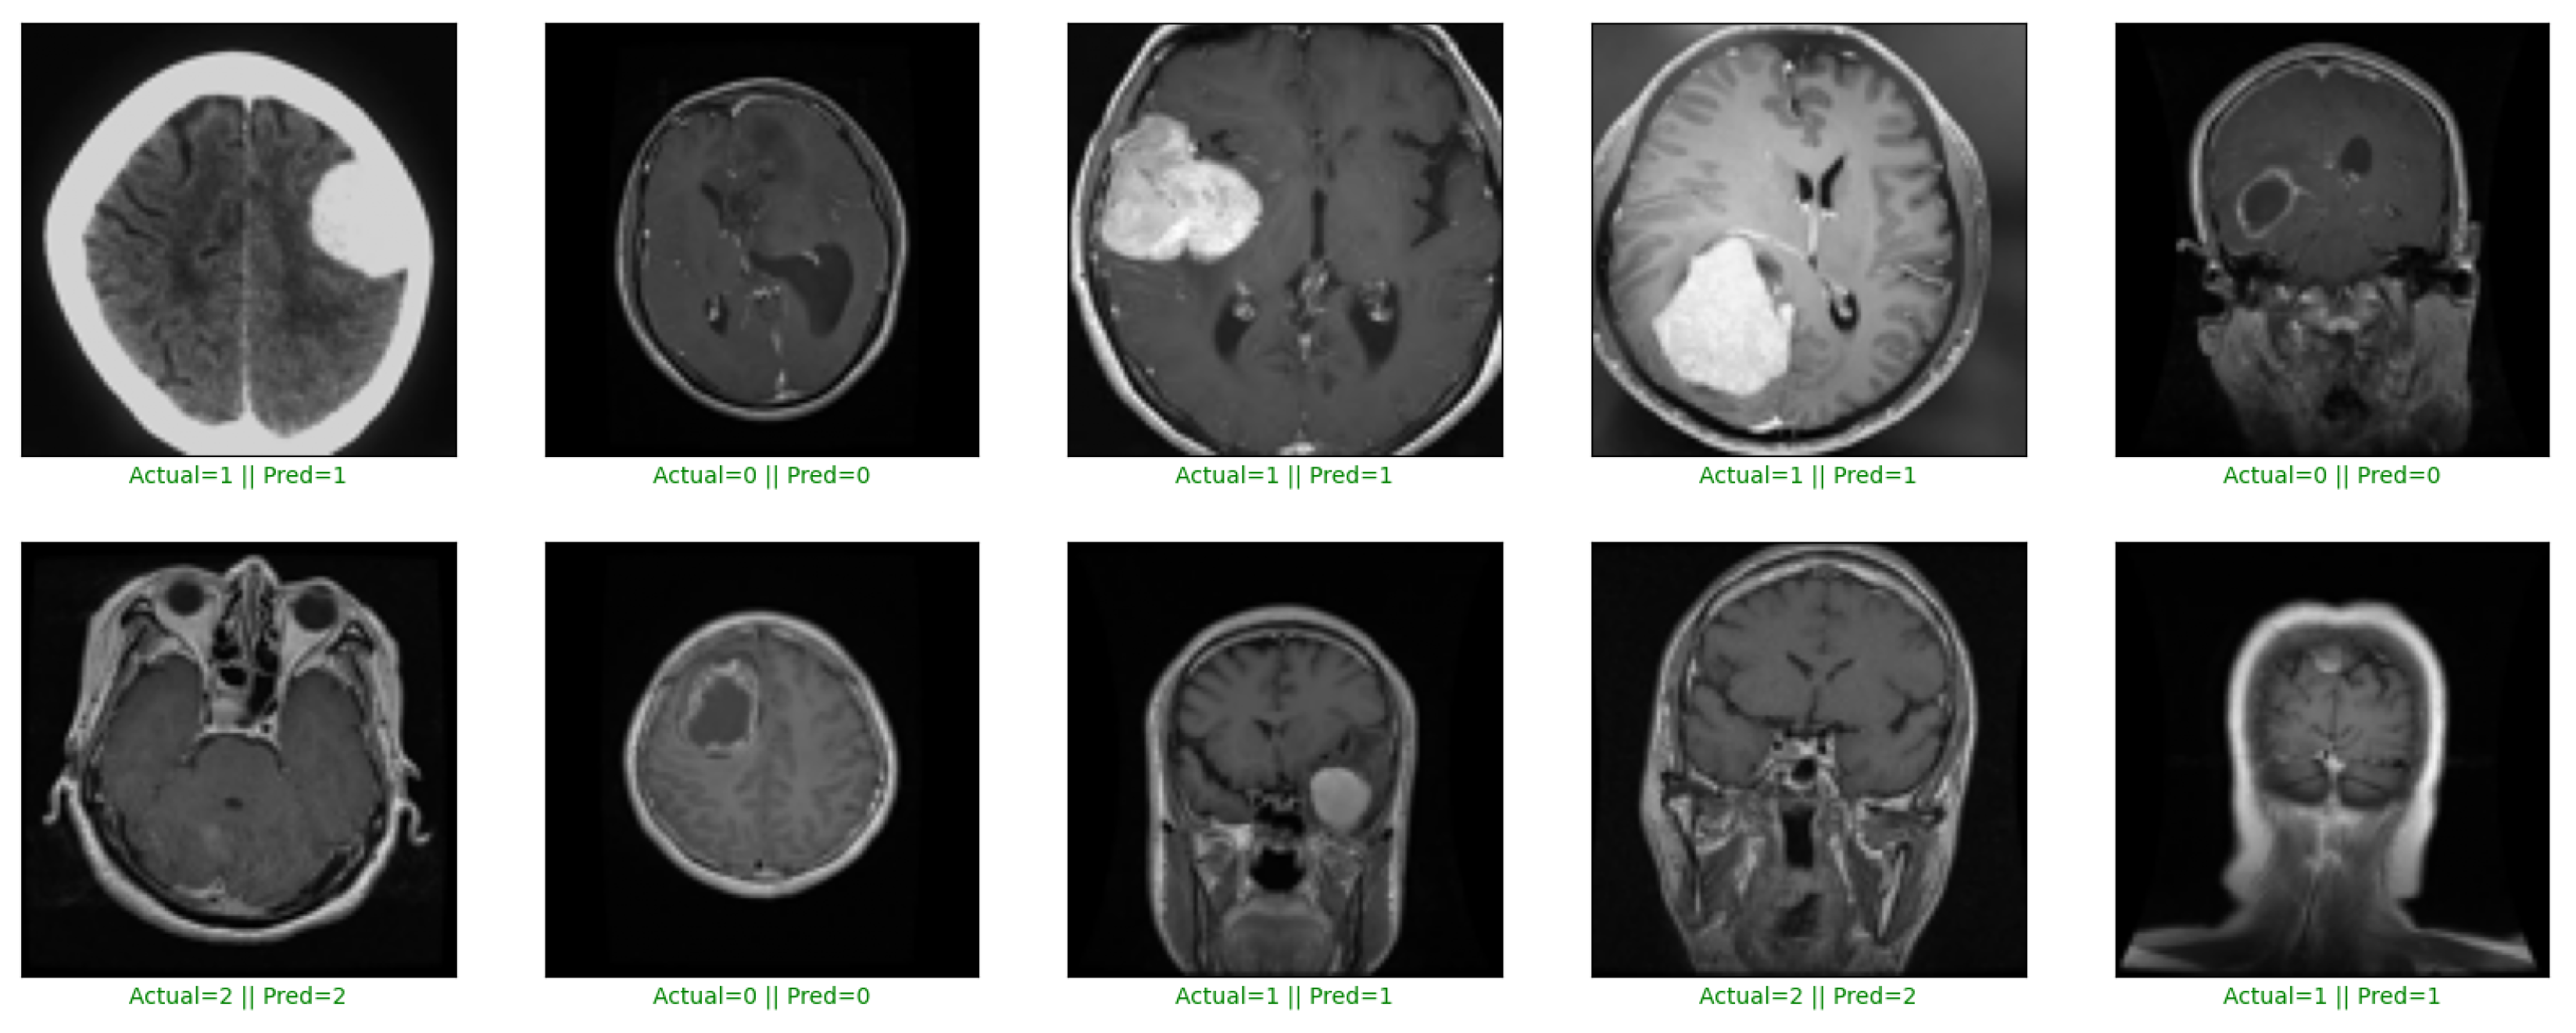

Furthermore, our model’s ability to efficiently and accurately distinguish between brain tumor and non-tumor images (as shown in Figure 3) is of paramount importance for clinicians, radiologists, and medical professionals. This high accuracy significantly reduces the risk of misdiagnosis, ensuring that patients receive the appropriate care and treatment. Furthermore, the adaptability of our model across diverse datasets improves its applicability in various clinical environments, making it a robust and reliable tool in the field of medical image analysis.

Figure 3.

Multi-modal brain tumor detection and classification on Dataset 1.